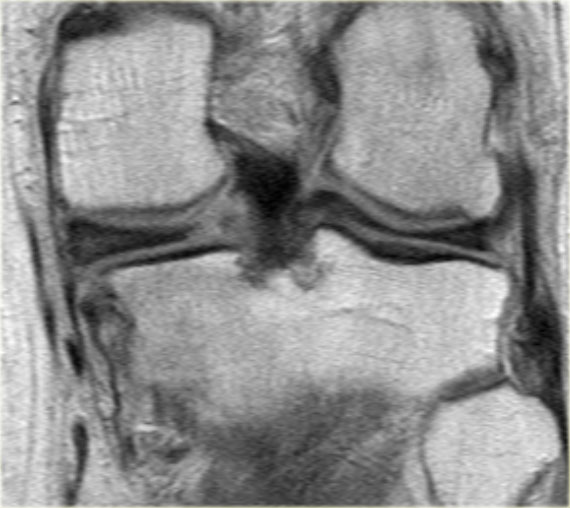

Bên trái là ba lát cắt coronal PD liên tiếp:

Rách bó dây chằng bên trong sâu (mũi tên vàng).

Bong mảnh xương ở mặt ngoài đầu gần xương chày, tức là gãy xương Segond (mũi tên đỏ). -

Lưu ý mảnh sụn chêm phía trong bị di lệch.

Điều này cho thấy còn có thêm rách dạng quai xô (bucket handle tear). -

Ngoài rách dạng quai xô (mũi tên xanh phía trong), còn có một đường rách ngang khó nhận thấy ở phần ngoại vi của sụn chêm (mũi tên xanh phía ngoài).

Đường rách ngang này được thể hiện rõ hơn trên các hình ảnh khác (không trình bày ở đây).